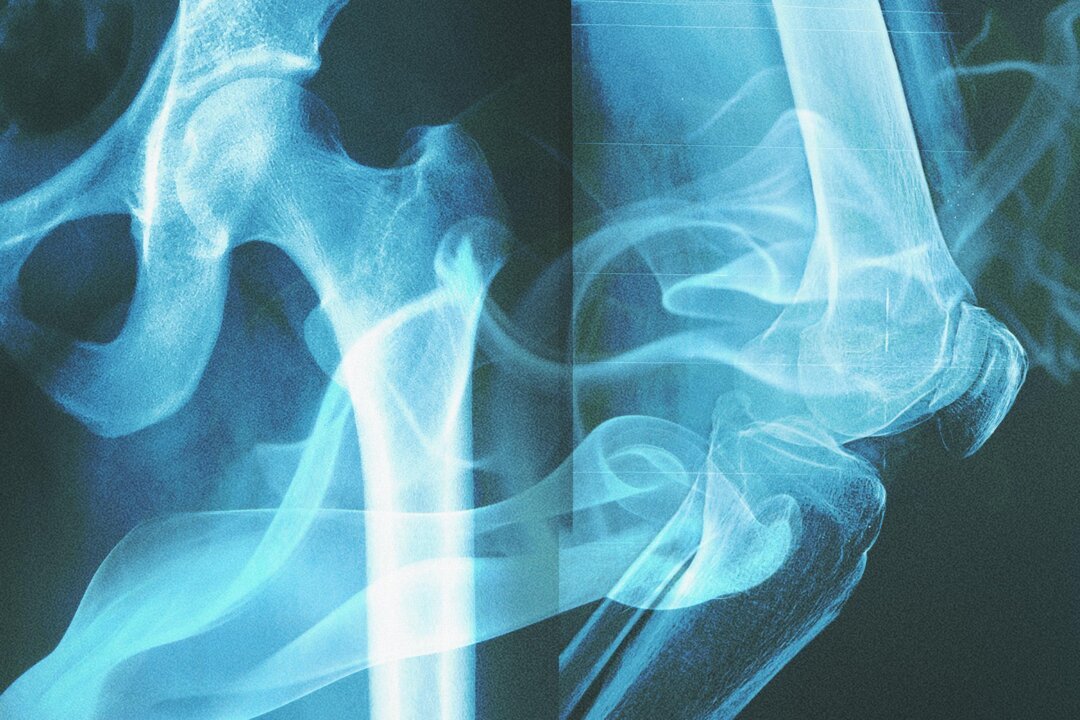

The concept of bones “remembering” cigarettes might sound mystical, but it’s rooted in solid biochemistry. When individuals smoke, the toxic compounds from cigarettes enter their bloodstream and eventually become incorporated into their bone matrix. This process creates permanent alterations in the bone’s molecular structure that serve as an unmistakable fingerprint of tobacco exposure.

These molecular signatures are so distinctive and durable that they survive the natural decomposition process, remaining detectable even in skeletal remains that have been buried for centuries. This discovery opens up entirely new avenues for both historical research and modern medical understanding.